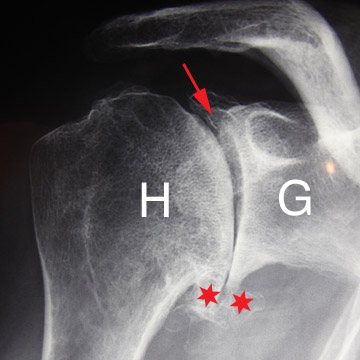

Le diagnostic se fait facilement sur de simples radiographies.

A long terme c’est la pièce glénoïdienne qui pose le plus de problèmes de descellement. Ces descellements se voient sur les radiographies sous forme de liseré évolutif entre la prothèse et le ciment ou entre le ciment et l’os.

Prothèse totale à 10 ans de recul.

Aucun liseré autour de la quille de la pièce glénoïdienne (flèches rouges).

Le liseré sous la surface articulaire n’a pas évolué depuis la pose (flèches vertes).